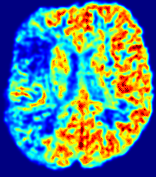

LesionRefer to captionRefer to captionRefer to captionRefer to captionRefer to captionRefer to caption𝐕rgbsubscript𝐕𝑟𝑔𝑏{\bf{V}}_{rgb}Refer to captionRefer to captionRefer to captionRefer to captionRefer to captionRefer to caption𝐕2subscriptnorm𝐕2{\|\bf{V}}\|_{2}Refer to captionRefer to captionRefer to captionRefer to captionRefer to captionRefer to captionRefer to caption3.53.53.52.82.82.82.12.12.11.41.41.40.70.70.70.00.00.0(mm/s)𝑚𝑚𝑠(mm/s)D𝐷DRefer to captionRefer to captionRefer to captionRefer to captionRefer to captionRefer to captionRefer to caption0.0200.0200.0200.0160.0160.0160.0120.0120.0120.0080.0080.0080.0040.0040.0040.0000.0000.000(mm2/s)𝑚superscript𝑚2𝑠(mm^{2}/s)Slice #1Slice #2Slice #3Slice #4Slice #5Slice #6

Figure 4: PIANO feature maps for another patient in the ISLES 2017 training set, where the lesion is located in the right hemisphere. Top row: segmented stroke lesion region (white) on different slices. The corresponding slices for the PIANO feature maps are shown in the following rows.

For a better insight into an estimated velocity field 𝐕𝐕{\bf{V}} and diffusion field 𝐃𝐃{\bf{D}}, we compute the following maps: (1) 𝐕rgbsubscript𝐕𝑟𝑔𝑏{\bf{V}}_{rgb}: Color-coded orientation map of 𝐕=(Vx,Vy,Vz)T𝐕superscriptsuperscript𝑉𝑥superscript𝑉𝑦superscript𝑉𝑧𝑇{\bf{V}}=(V^{x},V^{y},V^{z})^{T}, obtained by normalizing 𝐕𝐕{\bf{V}} to unit length and mapping its 3 components to red, green, blue respectively; (2) 𝐕2subscriptnorm𝐕2\|{\bf{V}}\|_{2}: 222 norm of 𝐕𝐕{\bf{V}}; (3) D𝐷D: scalar field in Eq. 5.

Fig. 3 and Fig. 4 show the PIANO feature maps estimated from two ISLES 2017 patients: all are highly consistent with the lesion in both cases. Details of the blood flow trajectories are revealed in 𝐕rgbsubscript𝐕𝑟𝑔𝑏{\bf{V}}_{rgb} by the ridged patterns and the sharp changes of colors in the unaffected (right) hemisphere, while the flat patterns appearing within the lesion provide little directional information about the velocity and indicate low velocity magnitudes. Velocity magnitudes are more directly visualized via 𝐕2subscriptnorm𝐕2\|{\bf{V}}\|_{2}, from which one can easily locate the lesion where 𝐕2subscriptnorm𝐕2\|{\bf{V}}\|_{2} is low. D𝐷D also indicates lower diffusion values in the lesion, though with less contrast potentially due to the fact that it captures the accumulated effect of CA diffusion at the voxel-level.